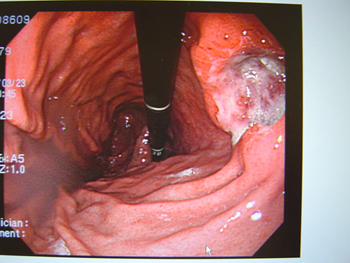

(a)上部消化管内視鏡

(胃カメラ)検査

ファイバースコープを口または鼻から挿入し,直接胃の中を観察します。がんの位置や大きさや拡がり,表面の形状や色調などを観察し,がんの一部を採取(生検)を行います。生検でとれたものは顕微鏡での検査(病理診断)を行い,確定診断します。